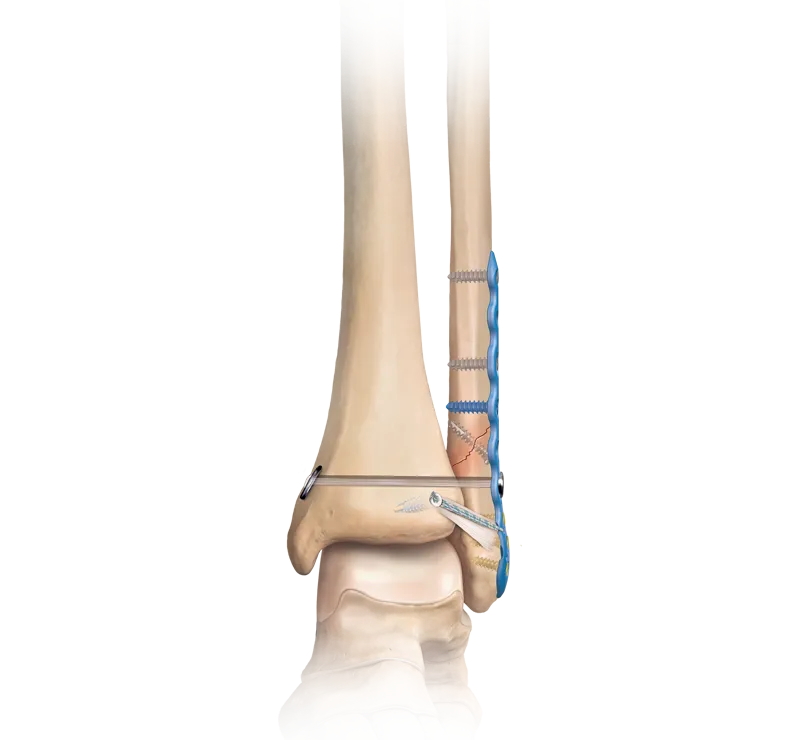

- Operative Treatment (ORIF):

- Indications: Unstable fractures, displaced fractures >2mm, open fractures, syndesmotic disruption, bimalleolar/trimalleolar fractures.

- Techniques:

- Lateral Malleolus: Anatomical plate & screws (lag screw if possible).

- Medial Malleolus: Cannulated screws, anti-glide plate, tension band wiring.

- Posterior Malleolus: Screws (direct posterior/posterolateral approach), buttress plate.

- Syndesmosis: Screws (e.g., 1-2 trans-syndesmotic screws, 3 or 4 cortices), suture button devices.